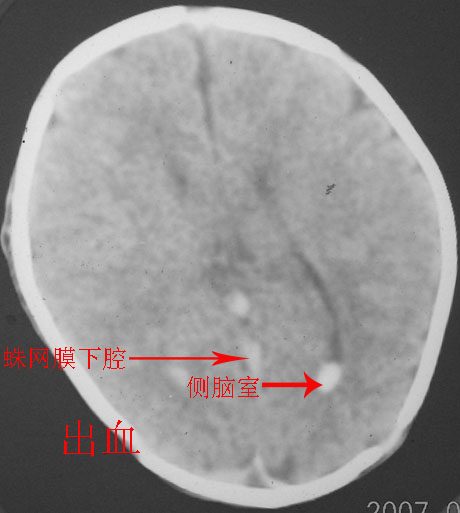

以下是引用rjg199343在2007-1-24 23:08:00的发言:[br]纵裂池、小脑幕、双侧脑室内高密度影,符合脑室、蛛网膜下腔出血。